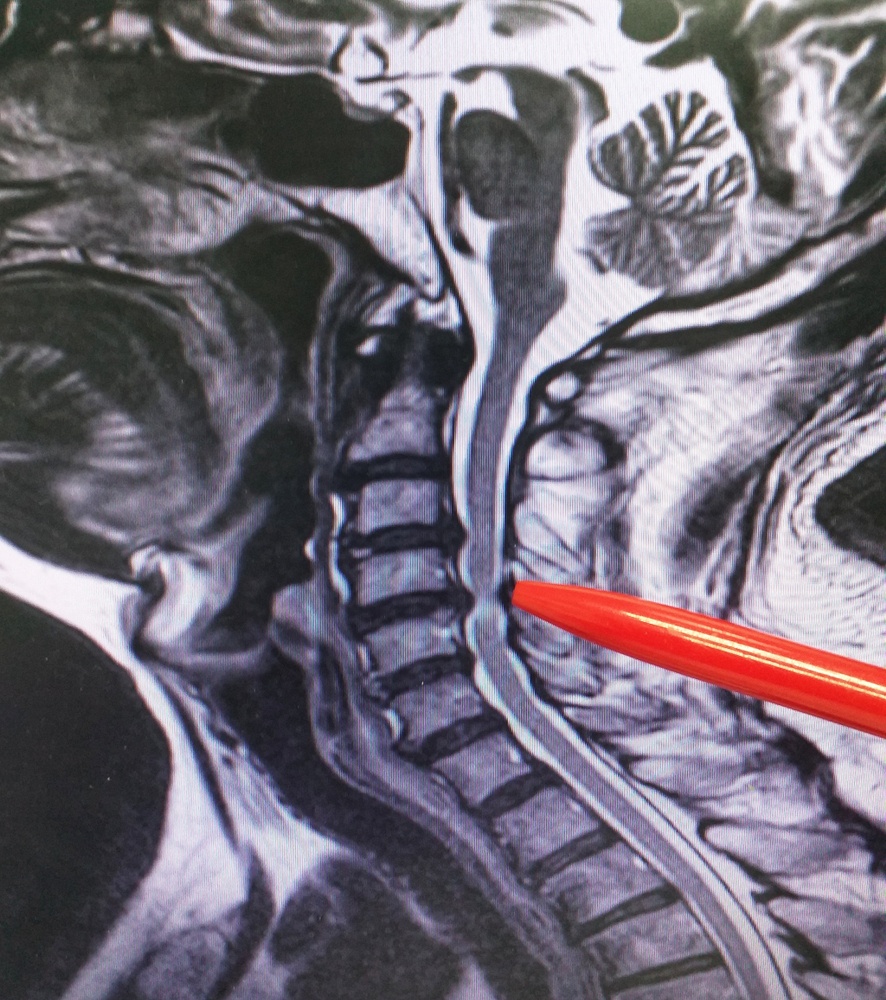

L’ernia cervicale si verifica quando un disco intervertebrale della colonna cervicale si altera e può comprimere una radice nervosa.

Questa compressione modifica la trasmissione degli impulsi nervosi e può influenzare:

- il movimento

- la sensibilità

- la forza muscolare